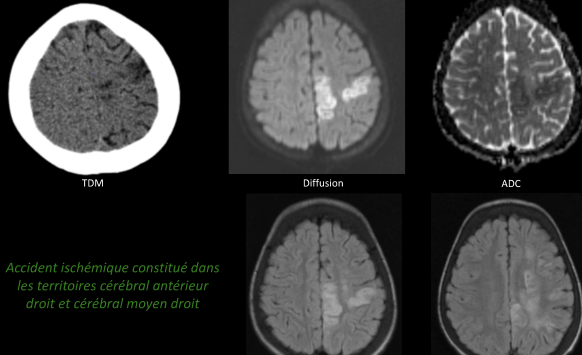

Cerveau

- AVCs ischémiques (200x risque)

- Troubles perfusionnels ++

- Sténoses vasculaires

- Territoires jonctionnels (Carotide++)

- Rarement Thrombo-emboliques